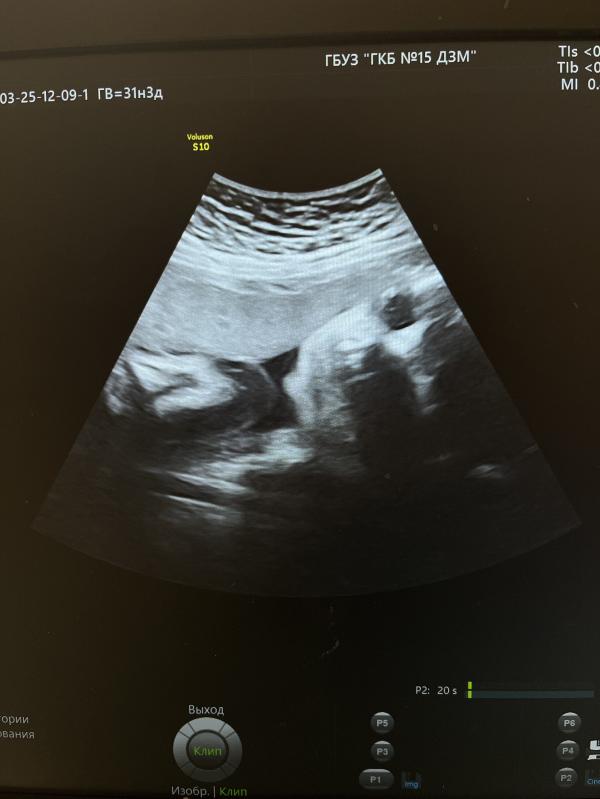

3 скрининг пройден

Вес 1755 +/- 256 гр

ЧСС 150 уд. в минуту

На 9 см выше внутреннего зева

Если еще почитать протокол УЗИ врача, то она пишет «В продольном положении в головном предлежании» и про пуповину «петель достаточное количество»